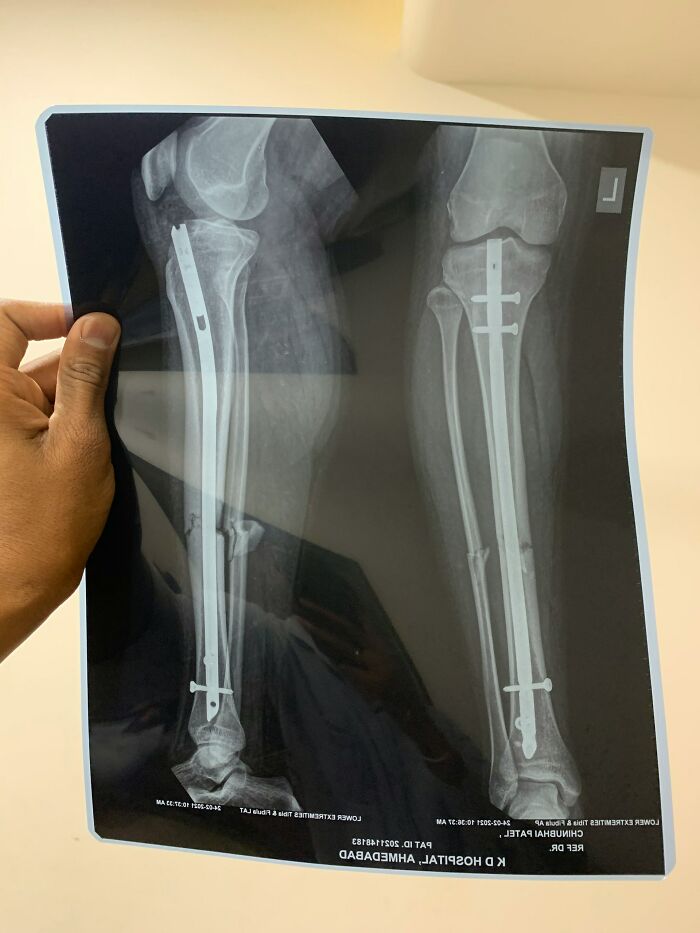

Worst thing id seen was someone come in complaining of leg pain and showing signs of septic shock. After examination dr orders scans and theres 2 metal rods (one in each leg) that weren't on their file. Turns out the patient has been to SE Asia to get a height altering surgery and the 'dr' had used items youd pick up from the local hardware store to fix the bones after breaking.

After extensive surgery patient lost the lower part of one leg and was lucky to keep the 2nd.

There’s patient information (name, ID) on that x-ray. Hope it’s fake.

Just clicked it, it's from a stock image website so completely unrelated to the story. Not sure about the patient info on it though.

Load More Replies...Those breaks are horrific too. And what's going on with that right fibula? I'm guessing that's the leg the patient lost?